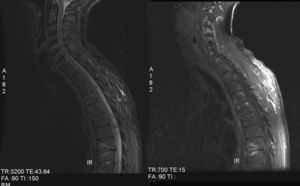

Hasta el momento se utilizan cuatro tipos de secuencias en el estudio de pacientes con espondiloartritis5. Una secuencia potenciada en T1 (utilizada para evaluar cambios estructurales y obtener imágenes que sirvan de guía anatómica), una secuencia T2 FSE con supresión grasa, una secuencia STIR (short tau inversion recovery) o una secuencia T1 con supresión grasa y administración de contraste paramagnético. Estas tres últimas son las que van a mostrar los hallazgos inflamatorios, bien al poner de manifiesto el edema de médula ósea (T2 y STIR) o bien al mostrar el aumento de vascularización que ocurre en las zonas con inflamación.

Los hallazgos inflamatorios aparecen en forma de lesiones hiperintensas en secuencias T2, STIR y con contraste paramagnético (fig. 1). La afección de articulaciones sacroilíacas suele ser unilateral al comienzo (de predominio en el sector ilíaco de la articulación), para luego hacerse bilateral y afectar también al sector sacro.

Los signos en la columna suelen localizarse en las zonas de transición cervicotorácica y toracolumbar, y afectan tanto a cuerpo vertebral, como a elementos posteriores vertebrales e incluso al disco intervertebral.